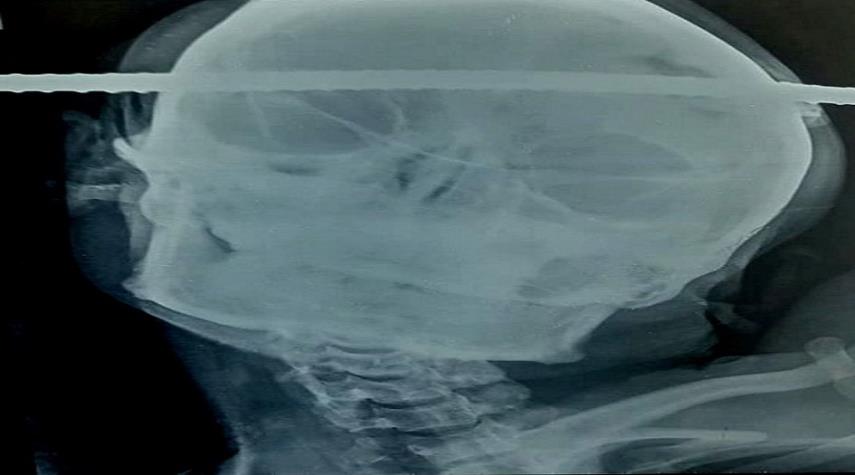

شاهد ...رجل ينجو من الموت بأعجوبة بعد اختراق قضيب حديدي رأسه !!

حوادث_الكوثر: